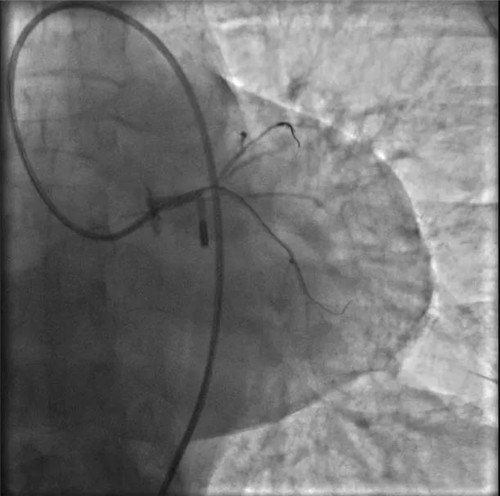

IABP(主動脈內(nèi)球囊反搏)

突發(fā)的狀況并沒有打亂團(tuán)隊的陣腳,待生命體征穩(wěn)定后,決定先植入IABP(主動脈內(nèi)球囊反搏)提供循環(huán)支持,防止病情進(jìn)一步惡化。穿刺雙側(cè)股動脈,分別置入IABP導(dǎo)管及左冠指引導(dǎo)管。

因患者股動脈扭曲,導(dǎo)管操控困難,術(shù)者反復(fù)嘗試,以導(dǎo)絲飄進(jìn)左主干,在球囊的支撐下,通過閉塞段到達(dá)中間支,小壓力擴(kuò)張后造影可見主干末端嚴(yán)重狹窄。隨后小心操控導(dǎo)絲到達(dá)回旋支、前降支,送入球囊擴(kuò)張,嚴(yán)重狹窄的左主干末端被撐開,左冠血流終于恢復(fù),胡女士暫時轉(zhuǎn)危為安。

球囊擴(kuò)張后,左冠血流恢復(fù),但左主干末端重度狹窄